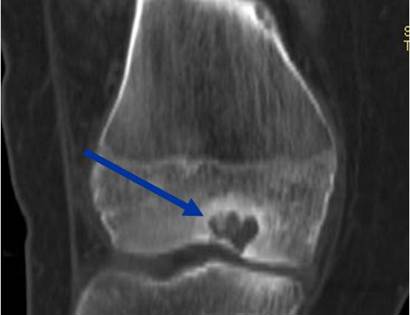

Radiographic imaging is used to help form a diagnosis of Chondroblastoma. Scans include X-Ray, MRI and Bone Scan. CT scan is sometimes used to assess the adjacent bone quality and look for flecks of calcium in the tumor to aid in diagnosis. MRI usually shows extensive swelling around the tumor that is sometimes misinterpreted as a cancer.